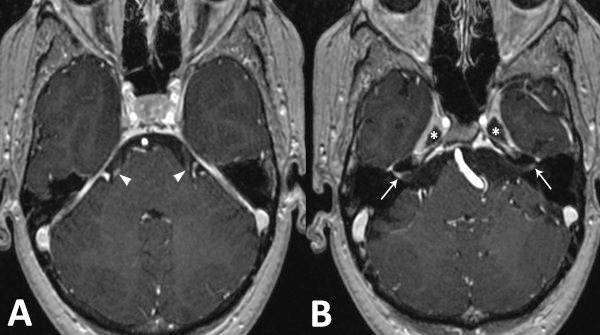

We present the case of a 40-year-old woman, with a confirmed erosive and seropositive RA, successfully treated by TNFα blocker (etanercept) for seven years, and who developed a severe neurosarcoidosis. She had lymphocytic meningitis, bilateral peripheral facial paralysis and anosmia, associated with bilateral hilar lymph nodes, papilloedema, anterior uveitis and elevated serum angiotensin-converting enzyme level. Magnetic resonance imaging showed a bilateral thickening of the Gasser's ganglia walls and enhanced signal of the vestibulocochlear, the facial and the proximal portion of trijeminal nerves.

我们介绍了一位 40 岁女性的病例,她患有明确的侵蚀性和血清阳性类风湿关节炎,经过 TNFα 阻滞剂(依那西普)治疗七年,成功缓解,随后发展为严重的神经结节病。她患有淋巴细胞性脑膜炎、双侧周围性面瘫和嗅觉丧失,伴有双侧肺门淋巴结肿大、视乳头水肿、前葡萄膜炎和血清血管紧张素转换酶水平升高。磁共振成像显示双侧鼓索神经壁增厚,前庭耳蜗、面神经和三叉神经近端信号增强。